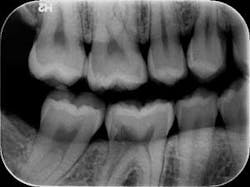

- This is another case of what could easily be misdiagnosed as internal resorption on tooth #No. 24. If you look closely in Figure 7, the outline of the canal can be seen.

- In Figure 8, the lesion is advanced significantly (one-and-a-half years had gone by) the irregular borders and moth-eaten appearance is easily observed.

- Definitive diagnosis: external resorption.